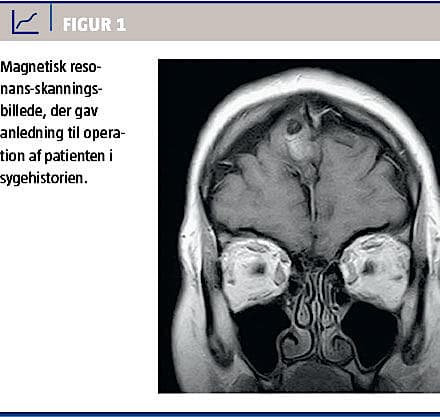

Pga. følelsesløshed og prikken under højre fod og senere bilateralt i arme og balder samt intermitterende svimmelhed blev en 37-årig kvinde vurderet af en neurolog. En magnetisk resonans (MR)-skanning afslørede en 3 cm stor tumor frontalt i subaraknoidalrummet uden sikker relation til meninges eller cerebrum samt 11 mindre tumorer, alle < 1 cm, under dura mater og langs falx cerebri (Figur 1). Tentativ diagnose var meningeomer, men pga. tumorernes atypiske udseende fandt man indikation for operation, den største tumor blev excideret, og symptomerne svandt. Histologisk diagnose var HO med trilaminær hæmatopoiese, en benign knogletumor. Patienten blev henvist til et endokrinologisk ambulatorium, hvor man fandt normale koncentrationer af P-calcium, fosfat, parathyroideahormon, 25-hydroxyvitamin D, osteocalcin og kreatinin. Koncentrationen af basisk fosfatase var normal, men koncentrationen af knoglespecifik basisk fosfatase var grænseforhøjet på 40 U/l (referenceværdi: 10-35 U/l). En knoglescintigrafi viste normale forhold bortset fra inhomogen knogleomsætning i os frontale på operationsstedet. Der var ingen tegn på HO i bindevævet og ingen hovedtraumer i anamnesen. Der blev ikke indledt farmakologisk behandling, og patienten blev fulgt med årlige kontrol-MR-skanninger for at observere eventuel vækst.